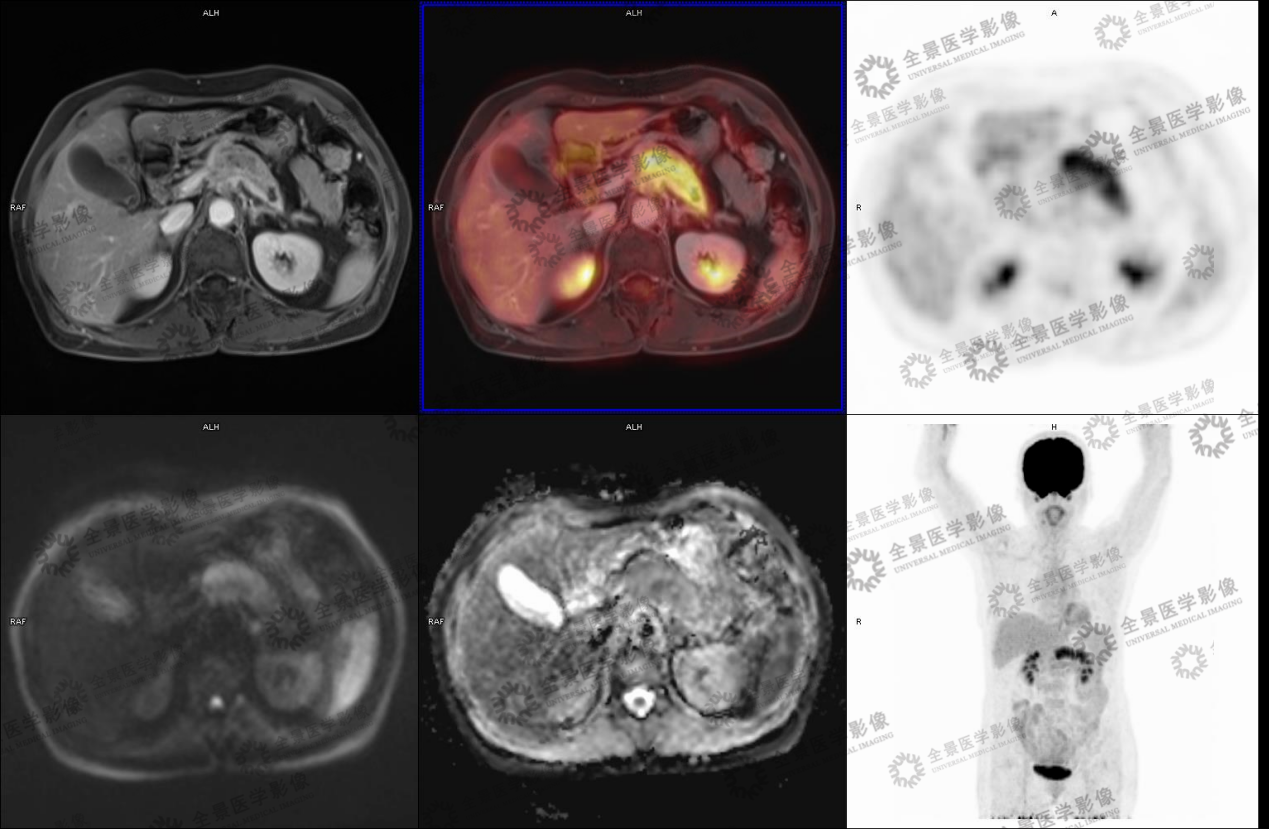

实例一

病史:女70岁 腹部不适,纳差半月,CT:胰腺MT伴小网膜囊淋巴结肿大及血管侵犯。

病灶呈延迟强化,FDG代谢增高,考虑胰腺癌。